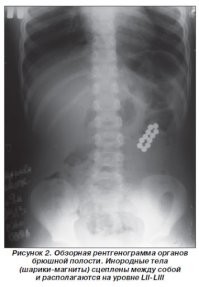

10-летняя Сэди Лэтем была срочно доставлена в Детскую больницу Олдер-Хей в Ливерпуле, где врачи сначала заподозрили у нее аппендицит. Однако, результаты рентгена показали, что в кишечнике ребенка находятся 15 магнитных шариков, склеенных между собой. Оказалось, девочка заснула с шариками во рту, притворившись, что у нее есть брекеты, как рассказала ее мать Кэтрин.

Мать не знала, что ее дочь проглотила шарики, пока три недели спустя Сэди не начала жаловаться на боли в животе. Лишь после этого девочку доставили в больницу, где ей назначили срочную операцию. В кишечнике ребенка магнитные шарики притянулись друг к другу, вызвав перфорацию - сквозное повреждение кишечника.